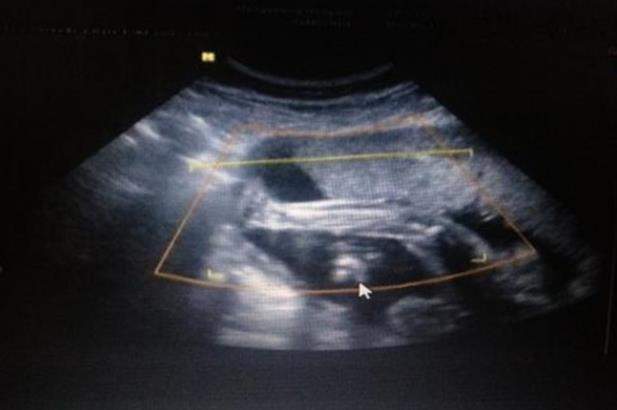

第三代试管婴儿技术是根据第一代试管演变而来,主要目的是增加患者做试管婴儿的成功率,第三代试管婴儿技术与第一代试管技术不同点在于第三代试管在移植前需要进行胚胎基因检测,一般是利用第三代试管来检测单基因遗传病和染色体疾病。